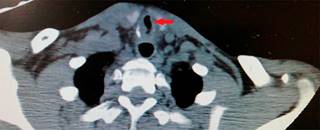

Se insertó un dispositivo supraglótico (mascarilla laríngea tipo supreme segunda generación), se realizó tomografía de cuello para visualizar el sitio y severidad de la estenosis, encontrando una disminución de calibre de la tráquea con luz de 5.1 mm (reducción comparada con segmentos previo y posterior, de 9.1 y 10 mm, respectivamente) (Figura 2).

Figura 2: Tomografía simple de cuello en corte axial. Ventana para tejidos blandos. Se muestra disminución del calibre de la vía aérea de 5.1 mm (línea roja señala la luz de la tráquea).